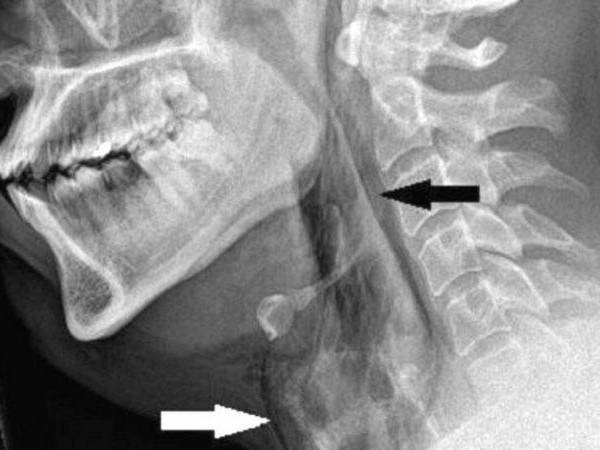

Un equipo médico emitió una advertencia después de que un hombre se perforara la garganta cuando intentó detener un estornudo.

El paciente, de unos 30 años, fue trasladado al hospital Ninewells, en Dundee, Inglaterra, con fuertes dolores, después de haberse apretado la nariz y cerrado la boca para reprimir el estornudo.

Las exploraciones revelaron que sufrió un desgarro de 2 mm en la tráquea.

Los médicos de la Universidad de Dundee dijeron que si se cierra la boca y la nariz durante un estornudo, la presión en las vías respiratorias superiores puede aumentar unas 20 veces.

Cuando los médicos examinaron al paciente, escucharon un crujido al tocarle el cuello y descubrieron que no tenía control de movimiento.

Un desgarro repentino de garganta, conocido médicamente como "ruptura traqueal espontánea", es poco común y puede ser potencialmente letal.